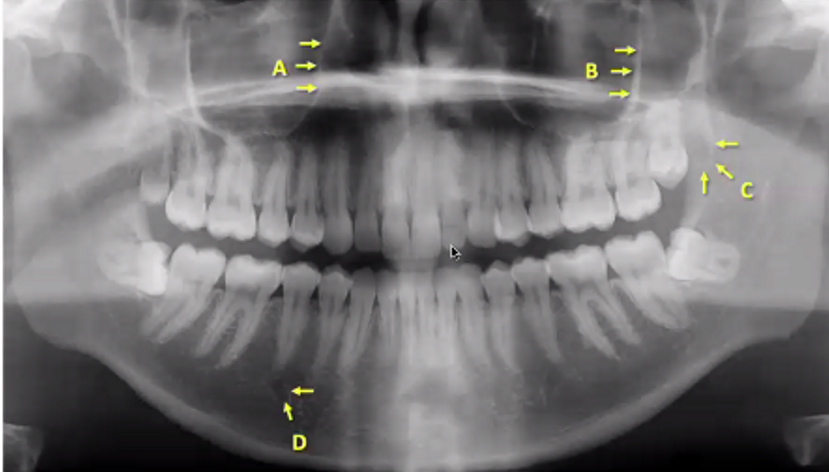

A

ethmoid sinuses

B

globe/eye

C

inferior concha

(meatus is the bone, here is inbetween so soft tissue)

D

Maxillary sinus